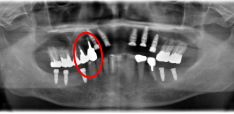

男性Kさん 50代(インプラント)

歯がグラグラするところ、むし歯のところ、しみるところ、被せ物がとれたところ、歯茎が腫れて血が出るところ、歯が抜けているところがある。すべて治したい。

治療内容

残っている歯を抜歯し、上下インプラント治療をしました。

所感

歯周病が進行している歯、むし歯が進行している歯がほとんどで、レントゲンを撮り、詳しく診てみると、ほとんどの歯を保存することができないことがわかりました。抜歯後は、入れ歯かインプラントの方法があります。治療開始前に患者さんに詳しく現状を説明し、治療法についてじっくり相談しました。自分の歯と同じような感覚で食事できるインプラント治療を選択されました。治療後、表情がとても明るくなり、口元がとても自然で10歳以上若返ったように感じました。「時間はかかりましたが、インプラントにして本当に良かったです!」と素晴らしい笑顔でお話ししてくださいました。

上顎:¥3,280,000(税込)

下顎:¥3,280,000(税込)